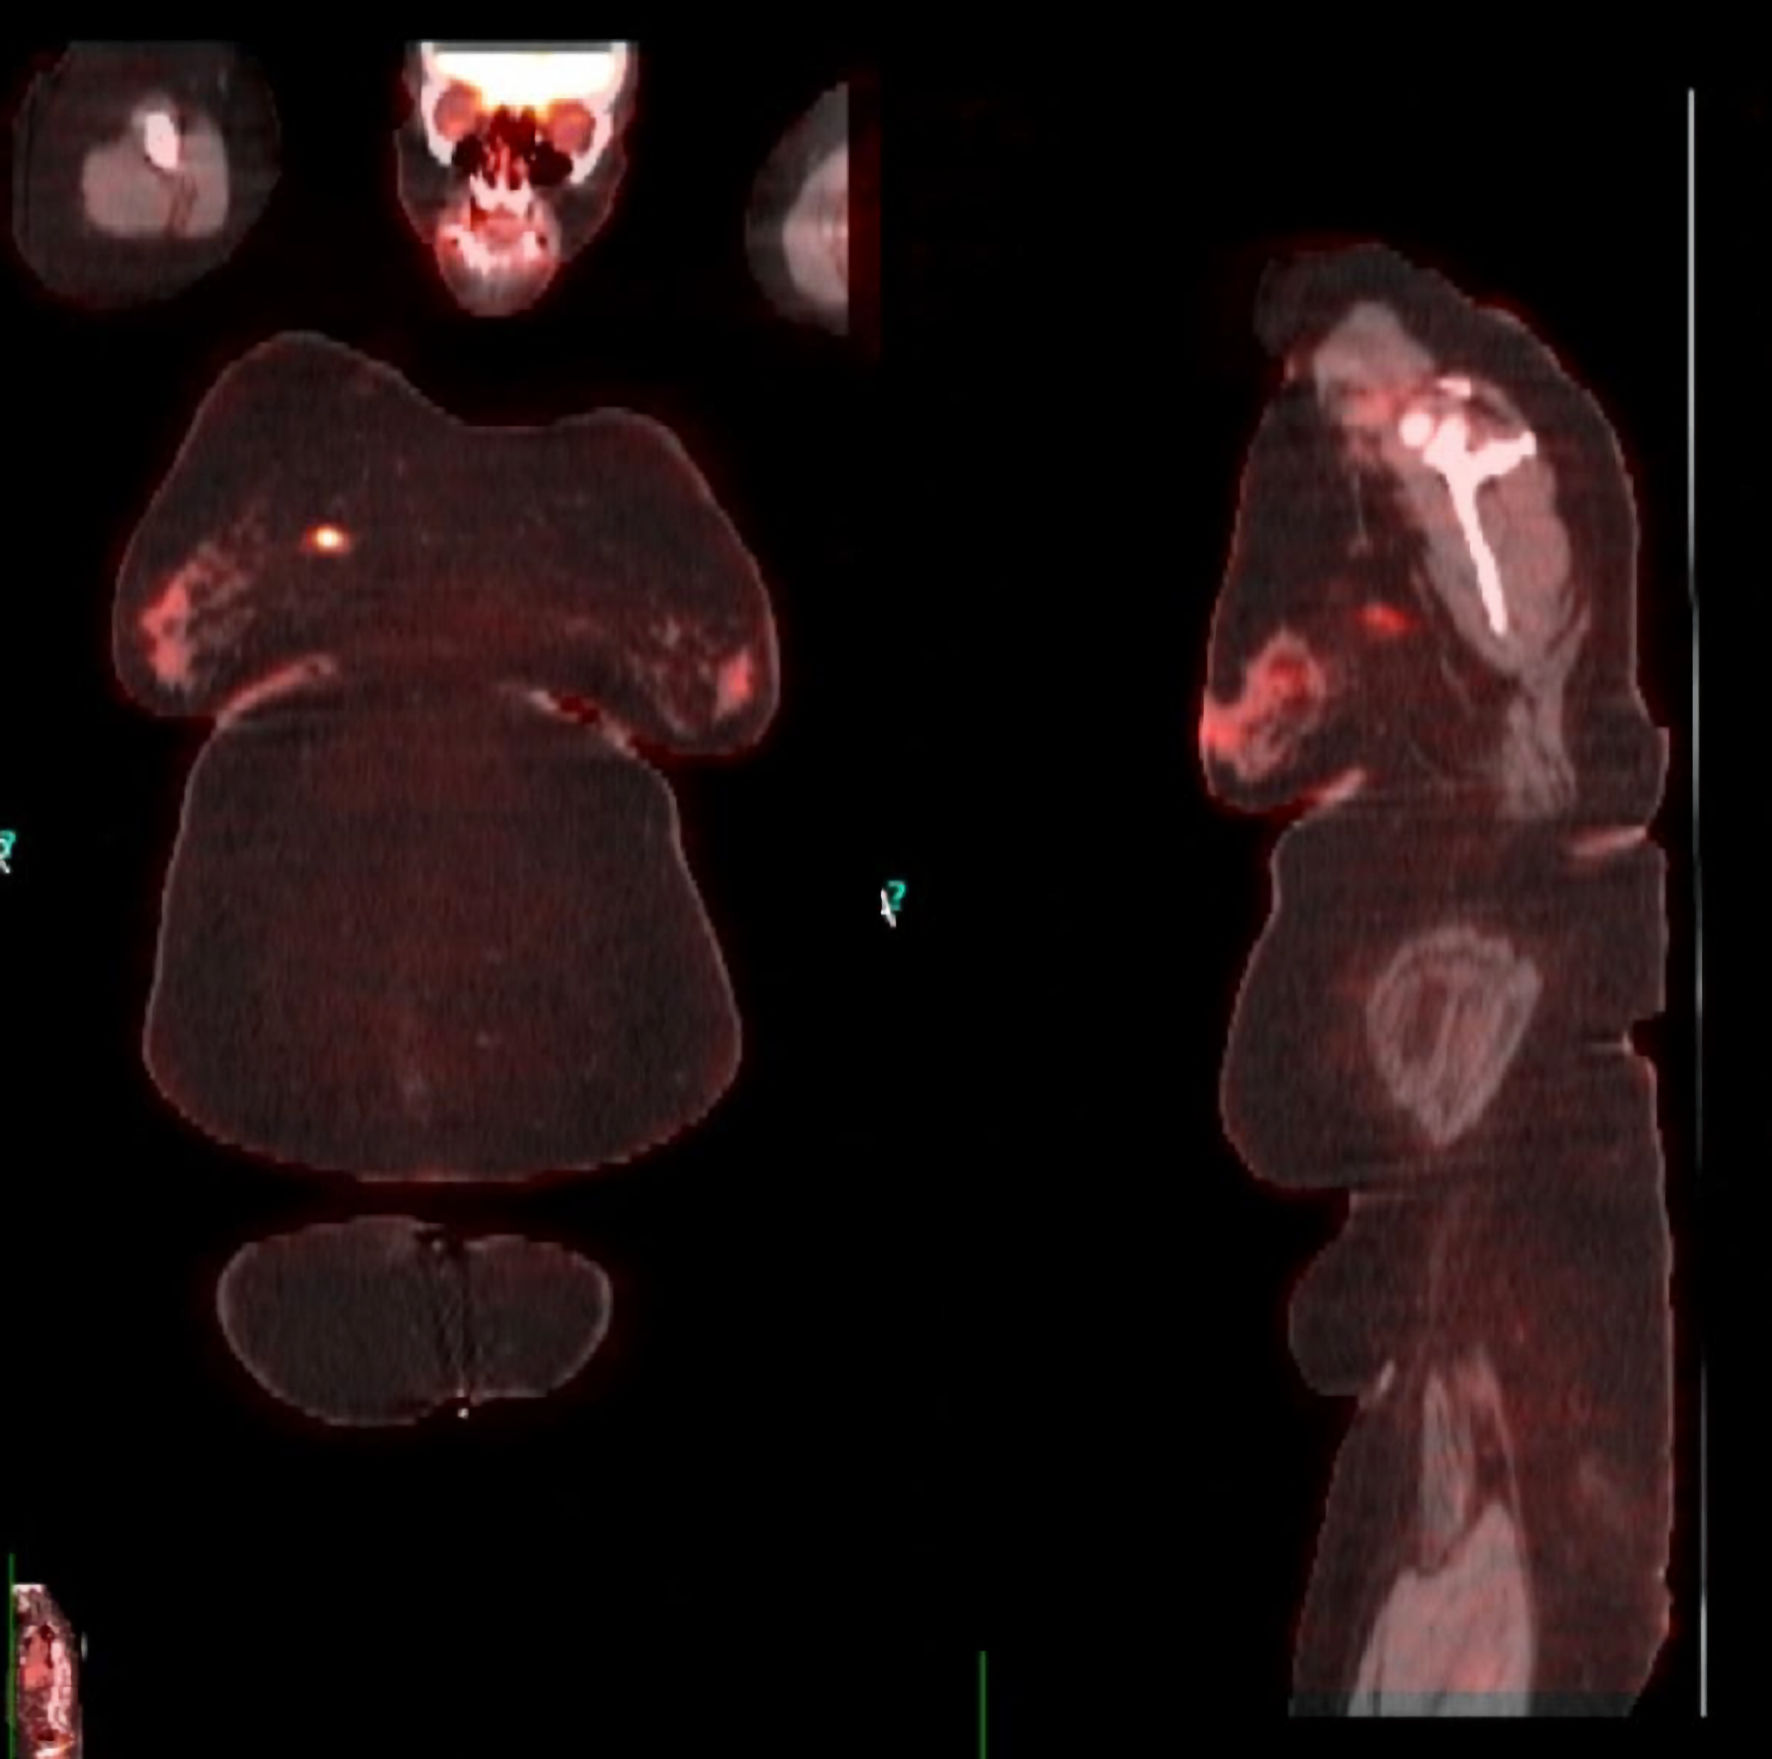

Bilateral diagnostic mammography showed a 1.2 × 1.9 cm right breast mass (upper inner quadrant) and a 1.9 × 2.1 cm left breast mass (upper outer quadrant). Breast ultrasound revealed a 1.3 × 1.6 cm heterogenous mass in the right breast with normal appearing right axillary nodes and a 1.8 × 2.1 cm solid mass in the left breast with an abnormal appearing left axillary node. Ultrasound-guided biopsy of the breast lesions showed invasive, poorly differentiated, high-grade ductal carcinoma with medullary features in the right breast, and poorly differentiated invasive ductal carcinoma in the left breast (Figs. 1, 2). The right breast lesion was negative for estrogen receptor (ER-) and progesterone receptor (PR-); the HER2/neu immunohistochemistry (IHC) score was 2+ but was positive by fluorescence in situ hybridisation (FISH) (percentage of positive nuclei > 90%). The left breast lesion was negative for ER, PR, and HER2 expression (triple-negative breast cancer (TNBC)). Staging workup with positron emission tomography/computed tomography (PET/CT) confirmed the lesions with a maximum standardized uptake value (SUV) of 6.2 in the right breast lesion and a left breast lesion with a maximum SUV of 17.6 in addition to a hypermetabolic left axillary lymph node with an SUV of 6.0 (Fig. 3). Genetic testing showed the presence of mutation in BRCA1 gene.

![]() Click for large image | Figure 3. PET/CT scan for staging confirming the lesions in both breasts. PET/CT: positron emission tomography/computed tomography. |